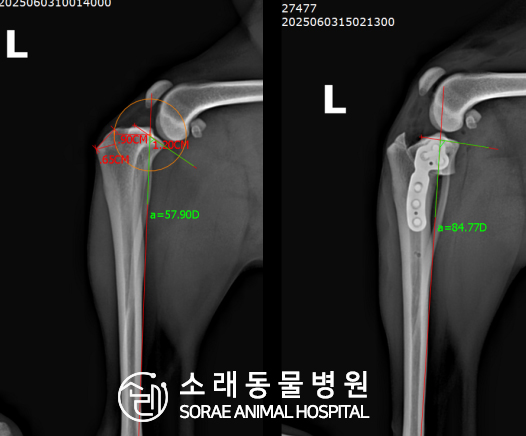

계산식으로 사전에 계획해두었던 플랜에 따라 경골을 절제하고

플레이트와 스크류를 사용하여 임플란트를 적용해 주었습니다.

반대 방향으로 밀려나 어긋나있던 대퇴골과 정강이가

제 자리를 찾으면서 무릎의 각도가 교정된 것을 확인할 수 있습니다